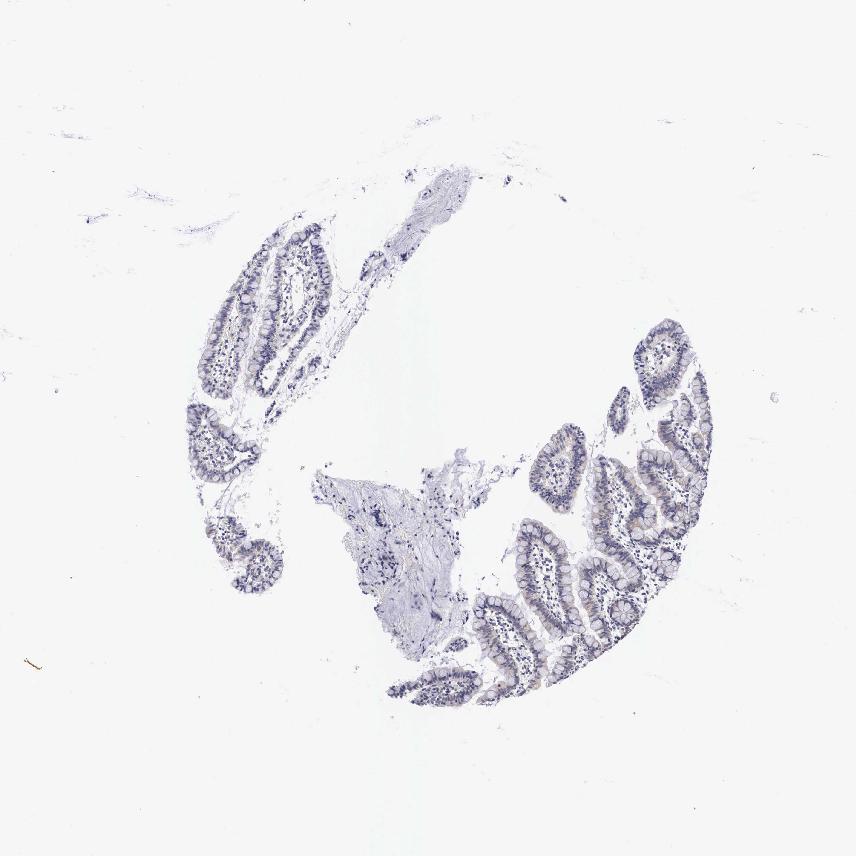

SMALL INTESTINE - Antibody stainingi

Antibody staining in the annotated cell types in the current human tissue is reported as not detected, low, medium, or high, based on conventional immunohistochemistry profiling in selected tissues. This score is based on the combination of the staining intensity and fraction of stained cells.

Each image is clickable and will lead to virtual microscopy that enables deeper exploration of all samples and also displays staining intensity scores, fraction scores and subcellular localization as well as patient and tissue information for each sample.

Antibody HPA000536Antibody CAB056152Antibody CAB056153

Glandular cells LowLowNot detected